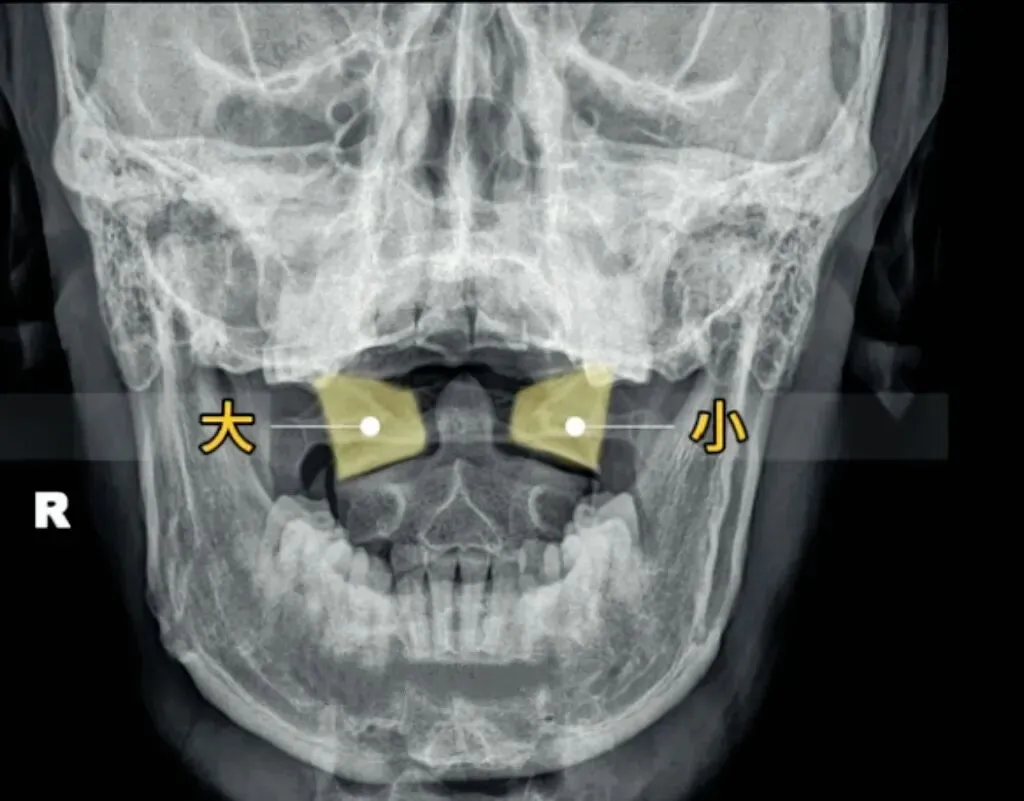

十张口是指寰枢椎的结构和位置关系,我们主要观察寰齿间隙和寰枢关节间隙及寰椎侧块的大小,来判断寰枢关节有无脱位的情况。

首先是寰齿间隙,如果枢椎与颈三的棘突位于同一条直线,

那么寰齿间隙哪边宽,就代表寰椎向哪边发生了侧方移位。

如果不在一条直线上,那就代表枢椎也有侧向的移动或旋转。

接下来是寰枢关节间隙,也称寰枢外侧关节,主要看两侧间隙是否等大,

如果一边宽一边窄,就代表寰椎向窄的一方发生了侧向倾斜。

再下来看寰椎侧块的大小,正常情况下侧块两边的宽度是等大的,

如果哪边侧块变大,就代表哪边的侧块向前方发生了旋转。